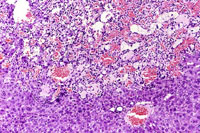

This hemangiosarcoma is well demarcated from the normal hepatic parenchyma; sharp demarcation is an unusual feature of hemangiosarcomas. Large blood-filled lakes are apparent. Higher magnification shows bands of spindle-shaped endothelial cells with attendant destruction of hepatocytes, proliferation of plump endothelial cells, and atrophy of hepatocytes.